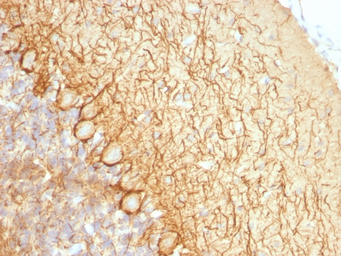

IHC-P analysis of rat cerebellum tissue using GTX34902 NF-L antibody [NR-4].